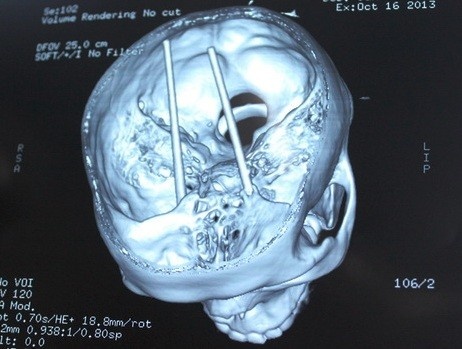

| Đôi đũa xuyên qua mắt tới não. |

Anh Dũng được chuyển đến bệnh viện Chợ Rẫy (TP.HCM) cấp cứu trong tình trạng hôn mê, máu chảy ở mắt. Phim chụp CT cho thấy 2 chiếc đũa dài gần 20cm cắm ngập từ hốc mắt qua sàn sọ, xuyên vào thân não.

“Đây là ca nặng nhất trong các trường hợp bị đũa đâm vào đầu mà Khoa Ngoại thần kinh tiếp nhận từ đầu năm đến nay. Ca phẫu thuật kéo dài hơn 5 giờ. Bệnh nhân không có máu bầm trong não nhưng đã bị dập não nên vẫn bị xuất huyết dọc đường đi của đũa. Rất may, các mạch máu lớn không bị đũa chọc thủng, nếu không thì khả năng tử vong rất cao”, bác sĩ Nguyễn Kim Chung, phó trưởng khoa Ngoại thần kinh của bệnh viện Chợ Rẫy, cho biết.